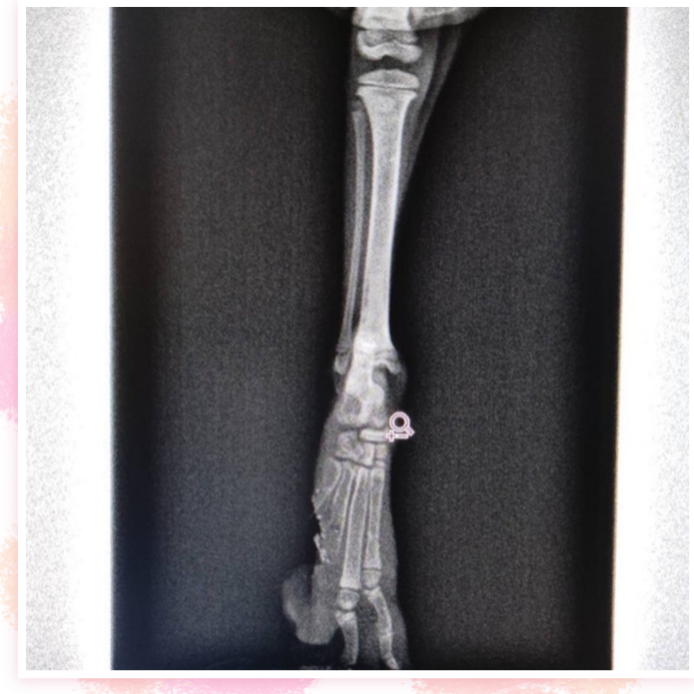

昨日、沖縄から負傷猫ちゃんの保護依頼が来ました。

まだ430gのちいちゃい子です( ; ›ω‹ )

遺棄されていたそうです。。

なんと肉球がパックリ2個切れてるそう。。

ボンネットに入ってか?何かに挟まれてかの事故

にあったのか?幸い骨折などはなく歩けるようです。

これから毎日消毒洗浄して、お薬を塗って

回復を待ちます。

飛行機に乗れるようになったらこちらに来れます。

早く良くなると良いね。